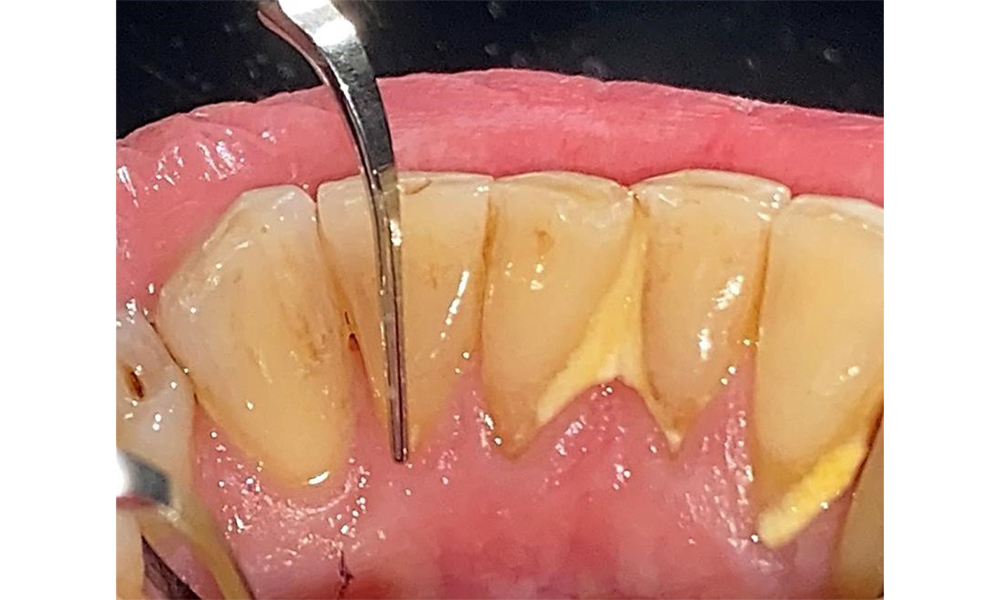

The documentation of periodontal findings, including pocket depth probing and bleeding status, is mandatory during each dental appointment due to the presence of periodontitis (Fig. 8). This will record the individual therapeutic needs and facilitate a rapid response to any progression of the pre-existing periodontitis.

Probing to document the findings in tooth 27 mesiopalatal. © Dr R. Krapf

Fig. 8: Probing to document the findings in tooth 27 mesiopalatal. © Dr R. Krapf